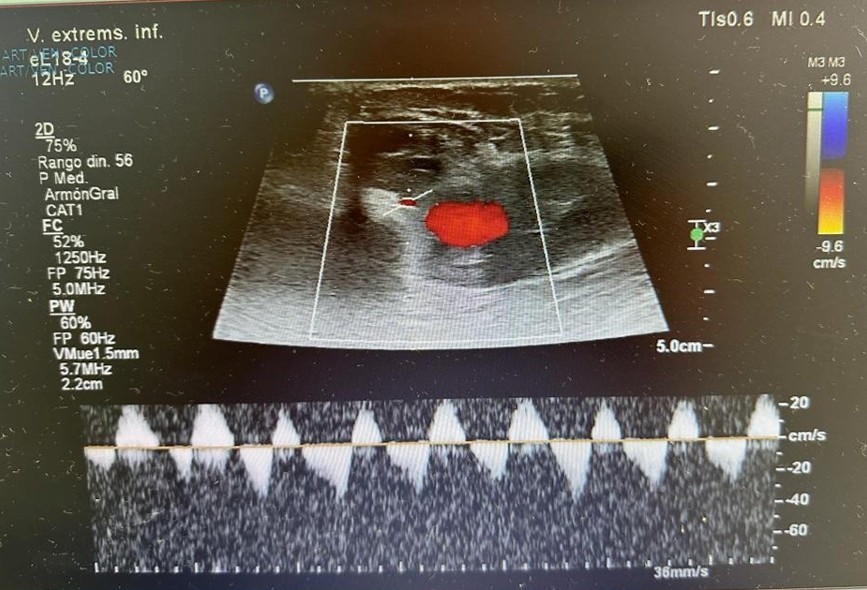

A las cuarenta y ocho horas del postoperatorio el paciente consultó por un cuadro de inflamación infrapatelar de la pierna izquierda. Ante la sospecha de una trombosis venosa profunda, se lo derivó de forma urgente a la guardia, donde se le realizó un ecodoppler venoso. El estudio descartó un proceso flebotrombótico, pero evidenció un hematoma que contenía signos compatibles con un pseudoaneurisma dentro del hematoma (Figs. 1 y 2). Frente a este hallazgo, se decidió realizar de manera urgente una angiografía del miembro inferior izquierdo, la cual confirmó la presencia de un pseudoaneurisma en una rama de pequeño calibre de la arteria poplítea, secundario a laceración traumática de dicho vaso (Fig. 3). En el estudio hemodinámico no se evidenció extravasación de contraste a nivel del pseudoaneurisma, motivo por el cual el equipo de hemodinamia lo consideró indemne.

Frente a este cuadro, el equipo de hemodinamia actuó de urgencia realizando una punción retrógrada de la arteria femoral común izquierda para efectuar una angiografía selectiva del miembro inferior izquierdo.

Se logró la embolización exitosa del pseudoaneurisma –de 13 mm de diámetro– mediante el uso de un microcatéter con tres microcoils (Fig. 4).

Figura 3. Arteriografía desde arteria poplítea derecha que confirma pseudoaneurisma de 13 mm de diámetro, del ramo genicular

Figura 4. Embolización selectiva de la rama genicular de arteria poplítea